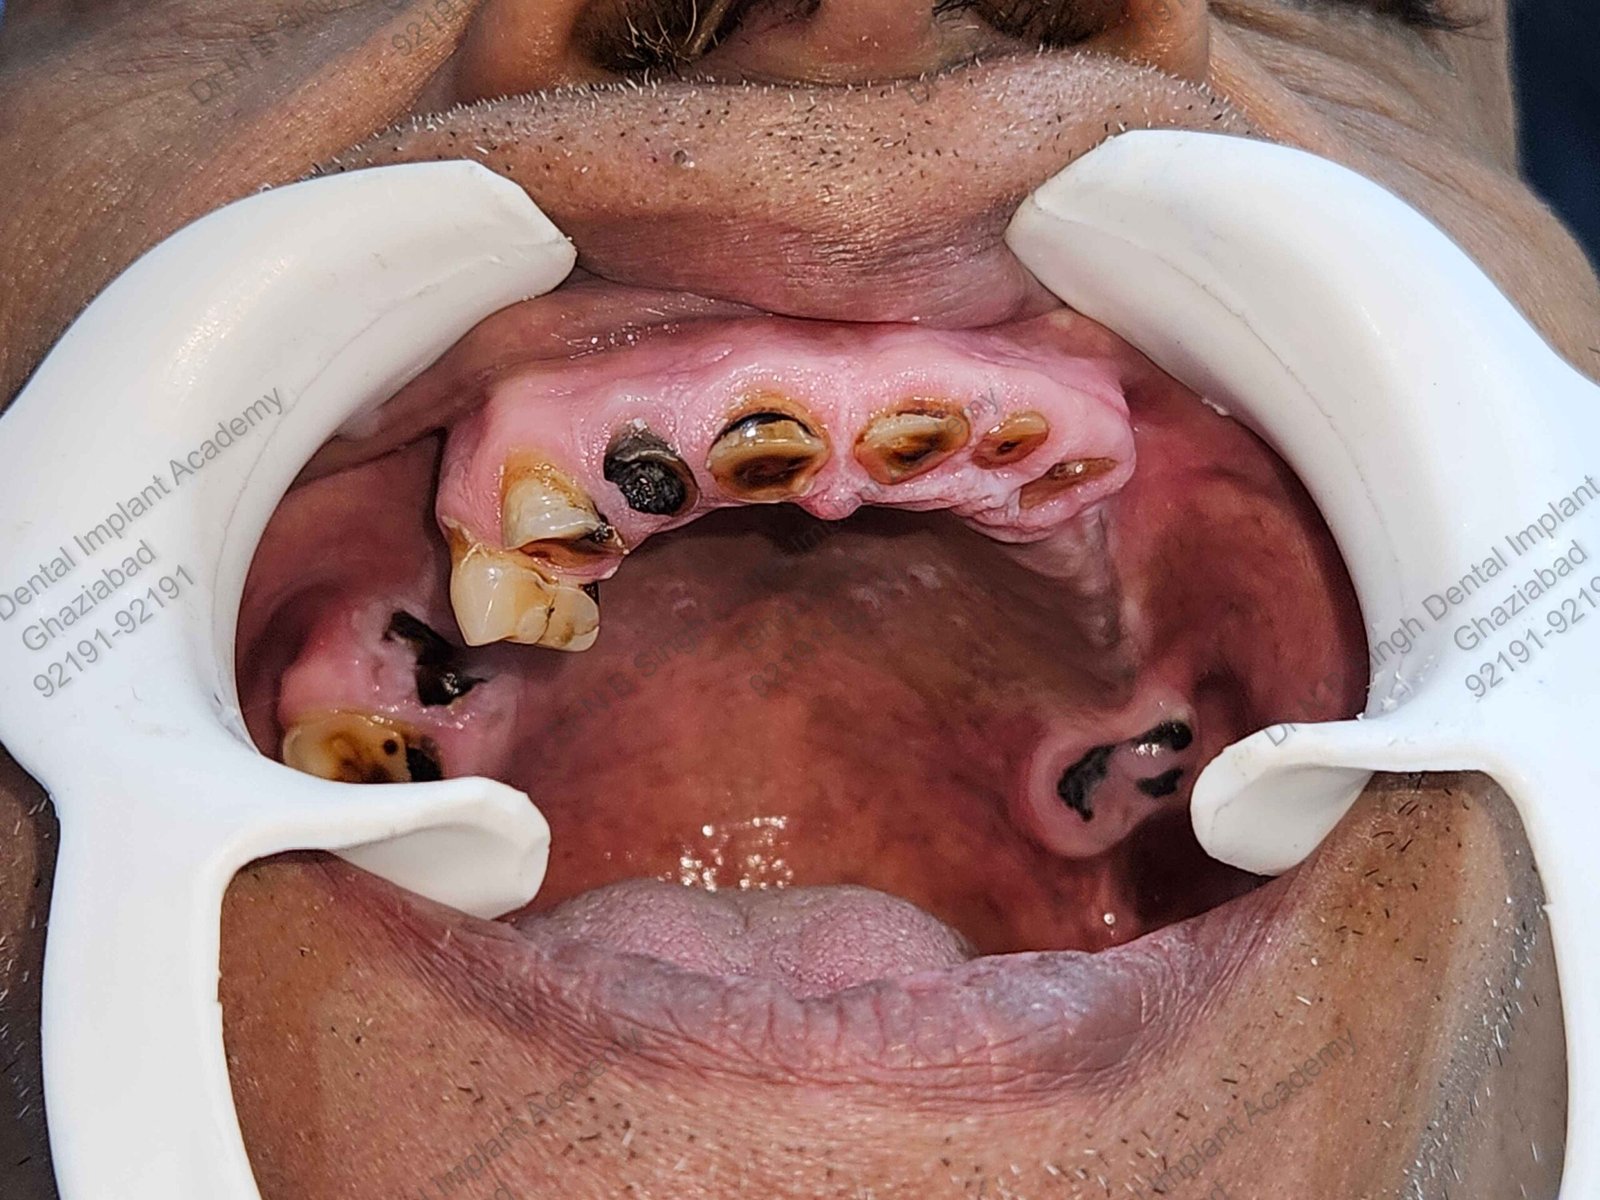

C1005 zygomatic basal implant full mouth – Ali Hasan 4

Dr. N.B. Singh